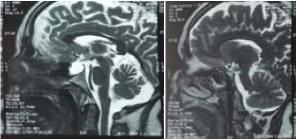

Nelson’s Syndrome: About 3 Cases

Gorgi K* 1 Chaouche M 1

Nelson’s syndrome is a severe complication that may develop in patients with Cushing’s disease treated with bilateral adrenalectomy. Since pituitary tumors in Nelson’s syndrome are often aggressive, early diagnosis and careful management are essential. We report three cases illustrating this syndrome.

Keywords: Nelson’s Syndrome; Pituitary Adenoma; Corticotroph Tumor; Adrenocorticotropic Hormone (ACTH); Bilateral Adrenalectomy; Cushing’s Disease;